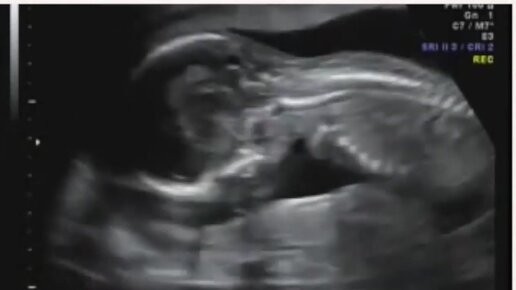

УЗИ на 16 неделе беременности

Медицинский женский центр